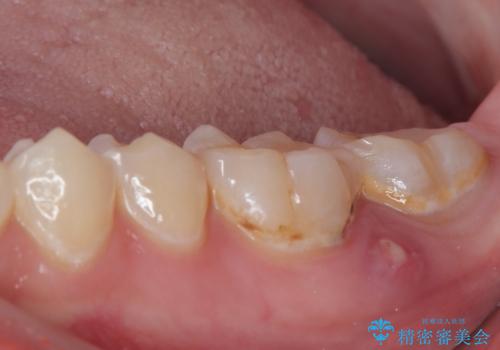

- 奥歯にものが挟まって痛みがあるとのことで来院された患者様です。

目視でも分かるくらいの欠損があり、歯の内部にむし歯が進行している状態でした。